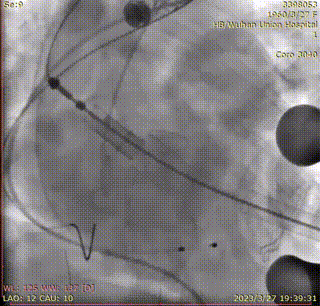

释放瓣膜:

复查根部造影,未见明显反流,瓣膜形态和位置满意,双侧冠脉未见遮挡征象: